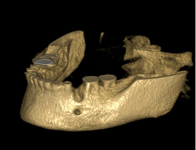

Tyto postupy nám umožní doplnit chybějící množství kosti v čelistech pacienta i zlepšit kvalitu kosti. Většinou se setkáváme s omezenou nabídkou kostní tkáně díky resorpčním (úbytkovým) procesům způsobených věkem či vytržením zubu, přítomností anatomických struktur jako je čelistní dutina, nervový kanál nebo patologických či poúrazových stavů - cysty, zlomeniny.

V těchto případech musíme použít některou z následujících pomocných metod:

použití umělého kostního granulátu

zahušťování kosti a její roztahování pomocí speciálních nástrojů spreading, kondenzace, distrakce

použití vlastí kosti nebo kostních štěpů - Transfer Set BEGO